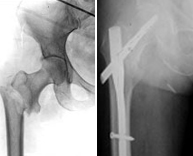

The pelvic ring articulates with the upper portion of the femur resulting in the "hip joint". The hip fractures are due to pelvic involvement in high energy trauma such as traffic accidents, falls from great heights and high speed sports. Fractures of the upper femur most common in elderly patients age and can be caused by minimal trauma due to osteoporosis. The huge range of fractures around the hip is large and therefore their treatments vary depending on the shape of the fracture. We advocate minimal invasive surgery through small incisions restoring the anatomy and returning the joint to its normal range of motion.